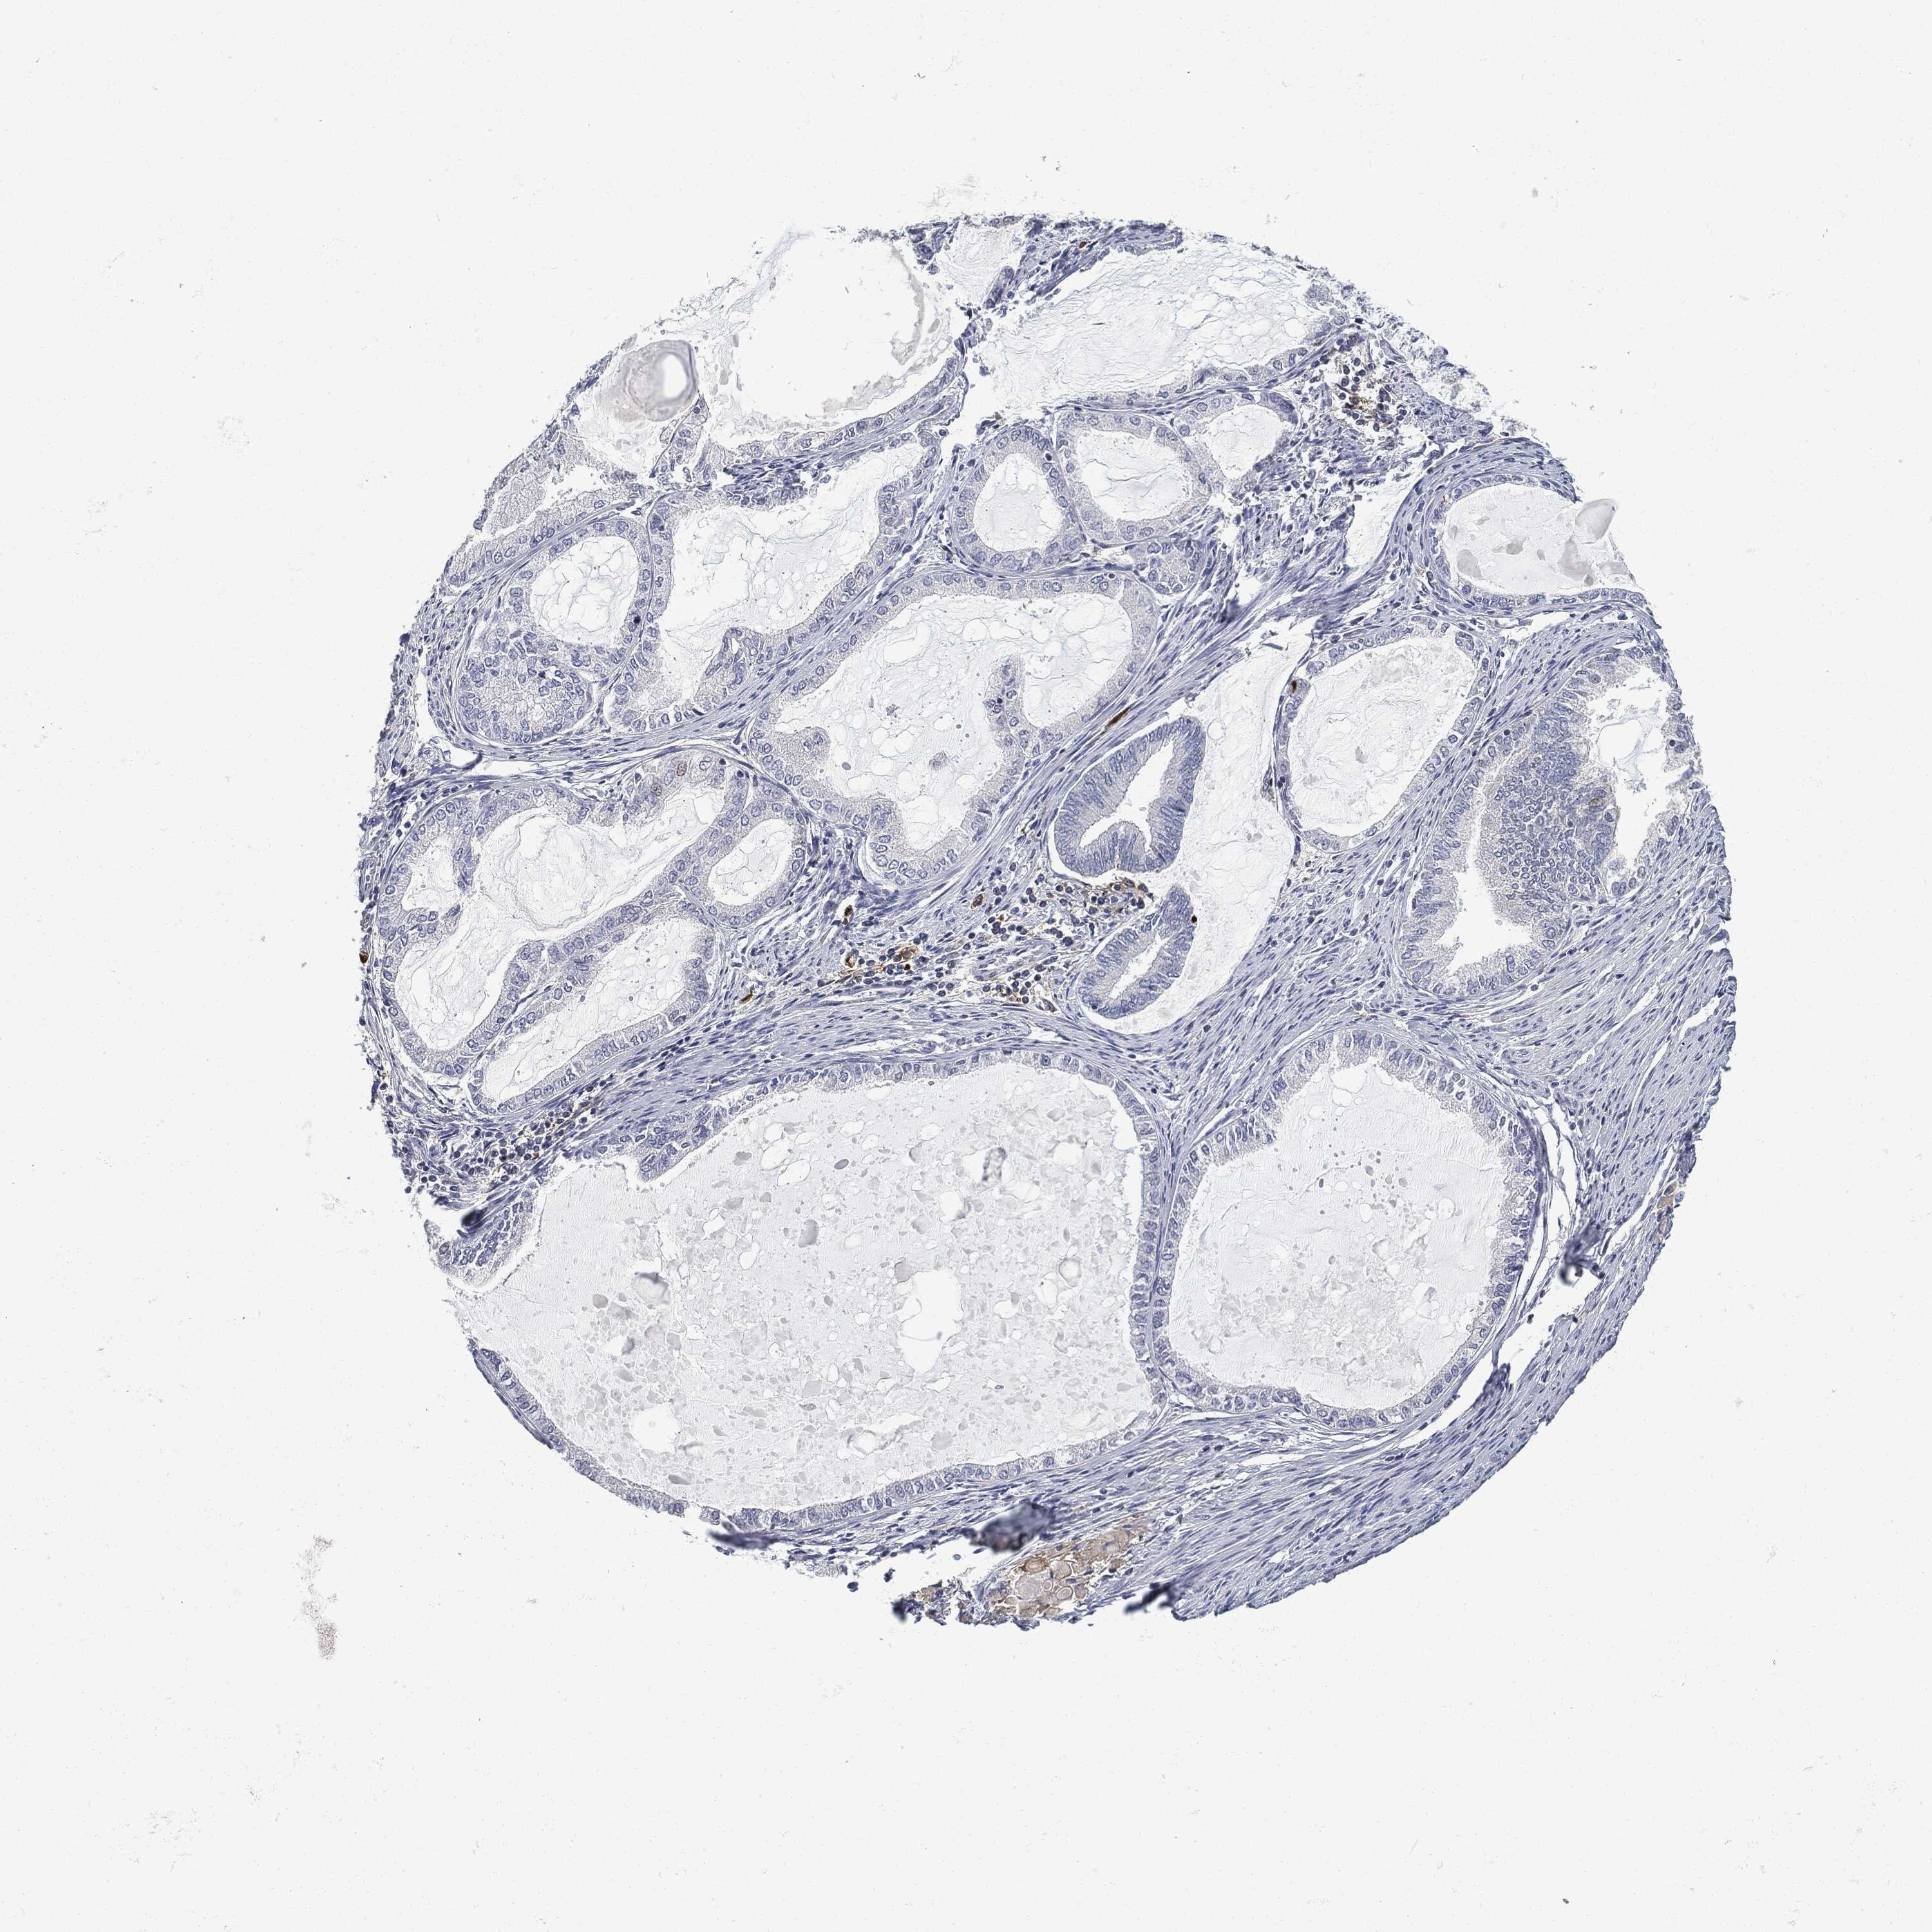

ENDOMETRIAL CANCER - Protein expressioni

A mouse-over function shows sample information and annotation data. Click on an image to view it in a full screen mode. Samples can be filtered based on level of antibody staining by selecting one or several of the following categories: high, medium, low and not detected. The assay and annotation is described here.

Note that samples used for immunohistochemistry by the Human Protein Atlas do not correspond to samples in the TCGA dataset.

Antibody stainingi

Antibody staining in the annotated cell types in the current human tissue is reported as not detected, low, medium, or high, based on conventional immunohistochemistry profiling in selected tissues. This score is based on the combination of the staining intensity and fraction of stained cells.

Each image is clickable and will lead to virtual microscopy that enables deeper exploration of all samples and also displays staining intensity scores, fraction scores and subcellular localization as well as patient and tissue information for each sample.

Antibody CAB076385

Antibody CAB080537

Staining

High

Medium

Low

Not detected

Intensity

Strong

Moderate

Weak

Negative

Quantity

>75%

75%-25%

<25%

None

Location

Nuclear

Cytoplasmic/membranous

Cytoplasmic/membranous,nuclear

Adenocarcinoma, NOS